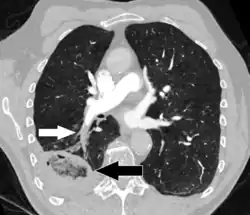

- Pulmonary embolism (white arrow) that has been long-standing and has caused a lung infarction (black arrow) seen as a reverse halo sign